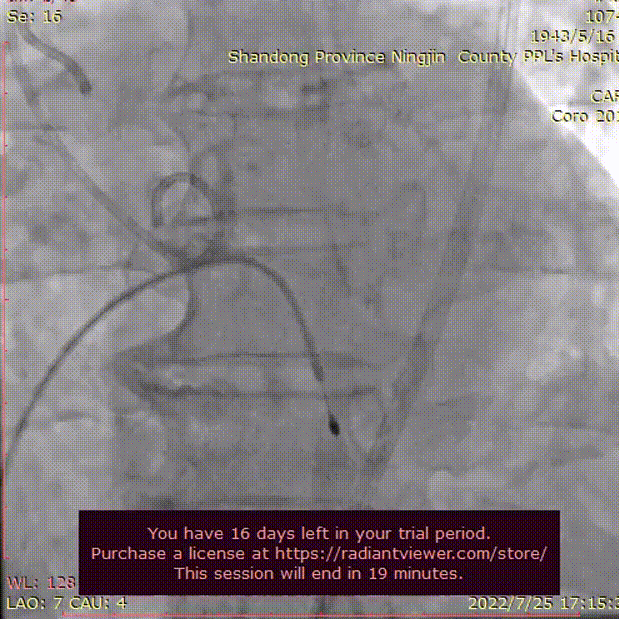

主动脉根部根部造影

造影评估

术者结合DSA影像,多角度观察瓣膜情况,在瓣膜释放至工作位造影。

初始定位释放

工作位

无明显返流,瓣膜形态佳,工作稳定。

工作位评估

完全释放